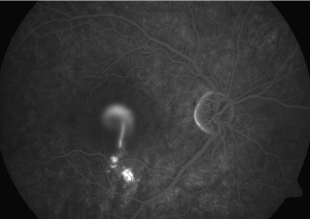

4. Angiografia fluoresceinowa (FA). Pozwala na lokalizację miejsca przecieku oraz kwalifikację typu CSCR do postaci prostej lub skomplikowanej. W przypadku postaci prostych zwykle mamy do czynienia z pojedynczym lub nielicznymi ogniskami przecieku, bez istotnych zaburzeń RPE. Postaci skomplikowane charakteryzują się licznymi ogniskami przecieku, czasami trudnymi do zidentyfikowania, obszarami PED oraz ubytkami w RPE. FA musi zostać wykonana w przypadku planowanej klasycznej fotokoagulacji laserowej miejsca przecieku.

5. Angiografia indocyjaninowa (ICGA). Umożliwia identyfikację obszarów wzmożonej przepuszczalności choriokapilar oraz stanowi najpewniejszą metodę diagnostyczną pozwalająca na planowanie PDT.

Zdjęcia angiografii fluoresceinowej oraz indocyjaninowej w ostrej i przewlekłej postaci CSCR. W dwóch przypadkach ostrych przeciek w FA przyjmuje formę kleksa lub snopu dymu. W postaci przewlekłej ogniska przecieku są trudne do zlokalizowania, bardziej widoczny jest „staining” siatkówki. W badaniu ICGA widoczna jest wzmożona przepuszczalność choriokapilar w fazie pośredniej angiogramu.